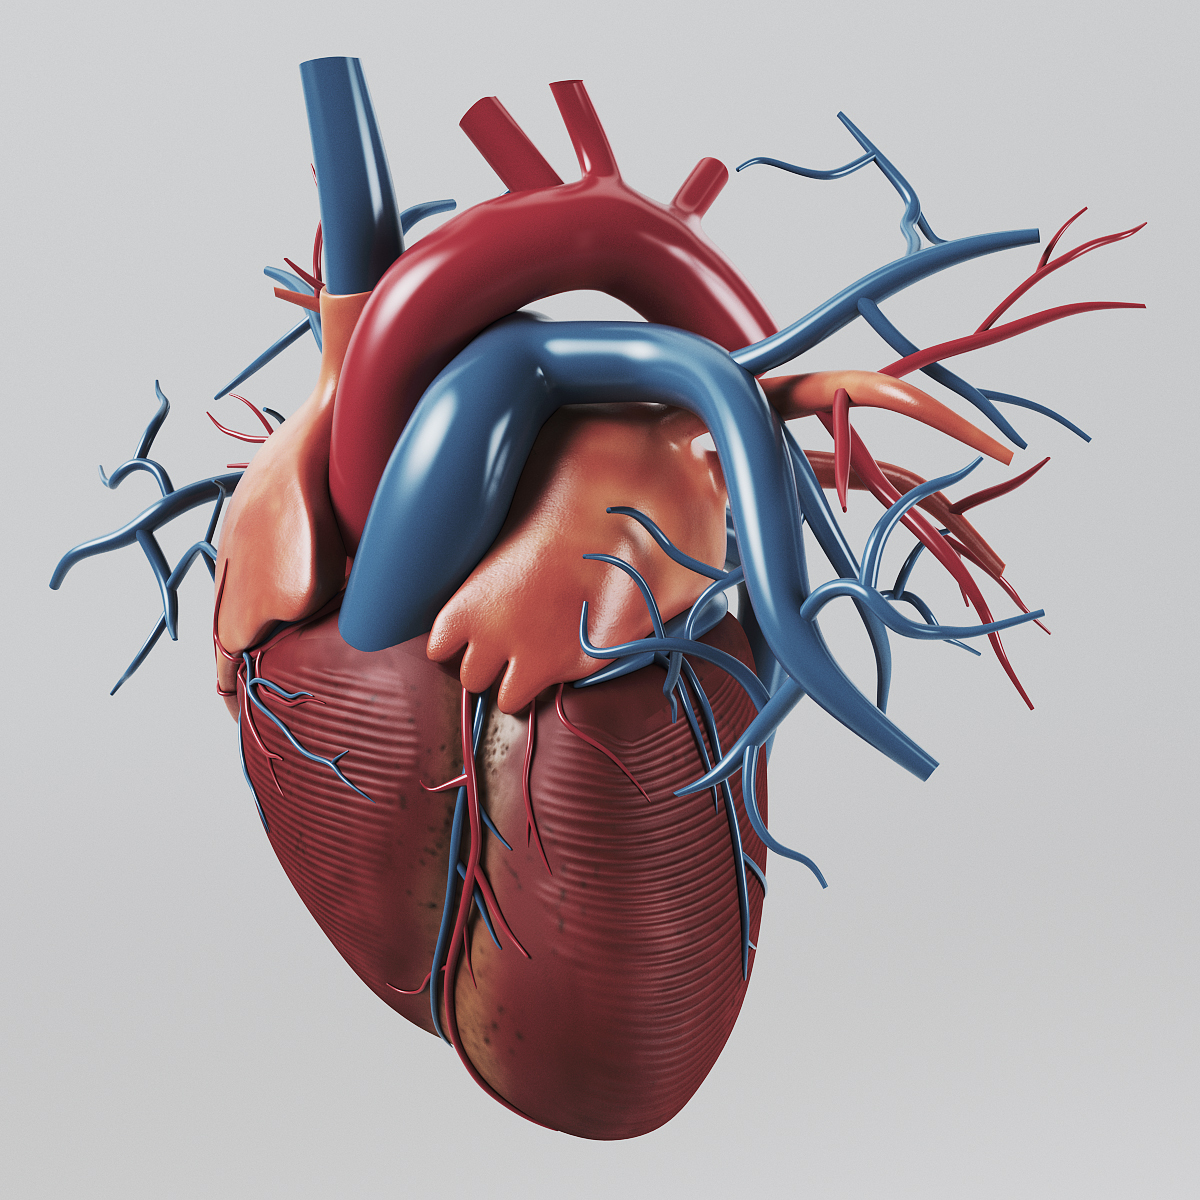

Human Heart Drawing Outline at GetDrawings | Free download  3d anatomy human heart

3d anatomy human heart  Show me a diagram of the human heart? Here are a bunch! - Interactive Biology, with Leslie Samuel

Human Heart Sketchbook study by bluesytealyren on DeviantArt | Human heart drawing, Anatomical  3d human heart

3d human heart  Animated Realistic Human Heart - Medically 3D asset

Animated Realistic Human Heart - Medically 3D asset  Zygote::3D Heart Model | Medically Accurate | Human Anatomy

Zygote::3D Heart Model | Medically Accurate | Human Anatomy  Zygote::Solid 3D Human Heart Model

Zygote::Solid 3D Human Heart Model  3D human heart anatomy model - TurboSquid 1283134

3D human heart anatomy model - TurboSquid 1283134  anatomy human heart 3d c4d

anatomy human heart 3d c4d  Modeled human heart section 3D model - TurboSquid 1657004